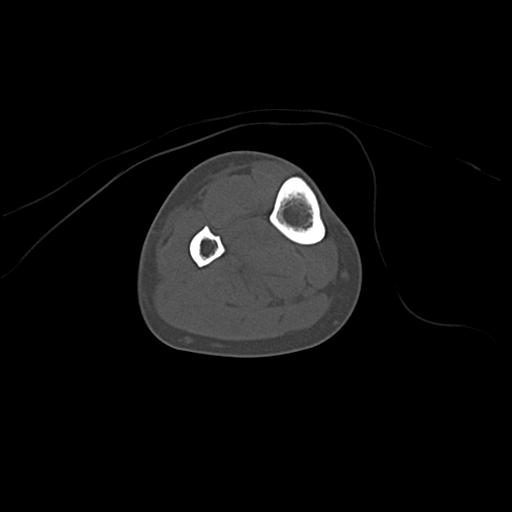

49554 3/13 膝 4R 3/16 4R 1/18 2R 78歳男性 膝蓋骨骨折